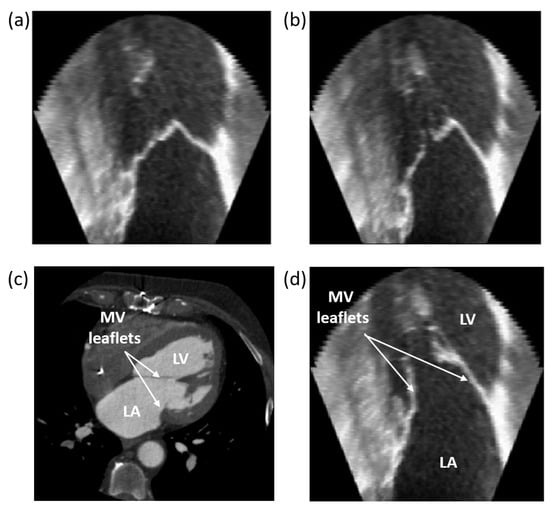

3.1. Case Study 1: Landmark Registration in Cardiology

3.1.1. CT/US Temporal Registration

3.1.2. CT/US Spatial Registration

4.1. Case Study 1